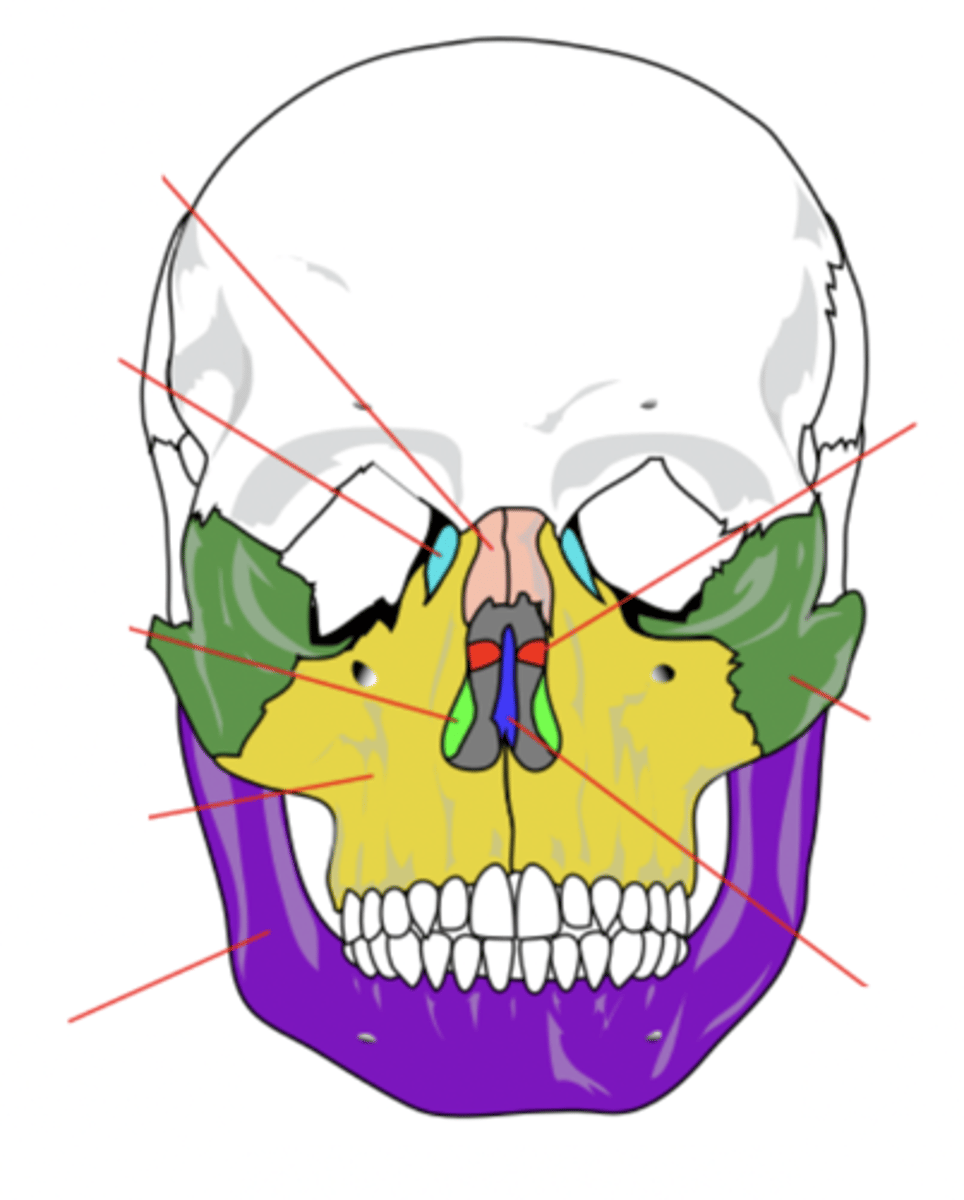

Facial Bones (14)

- Maxilla (2)

- Mandible

- Lacrimal (2)

- Palatine (2)

- Inferior conchae (2)

- Vomer

- Nasal (2)

- Zygomatic (2)

(Many Mammals Like Playing In Very Nice Zoos)

Maxilla Bone (2)

Upper jaw bone (yellow)

Mandible Bone

Lower jaw bone (purple)

Lacrimal Bone (2)

Small fragile bone making up part of the front inner walls of each eye socket and providing room for the passage of the lacrimal ducts (light blue)

Palatine Bone (2)

Bone that forms the hard palate and parts of the nose and orbits (red)

Inferior Conchae Bone (2)

The thin, scroll-like bones that form part of the interior of the nose (light green)

Vomer Bone

Bone that forms the inferior portion of the nasal septum (blue)

Nasal Bone (2)

Bone that forms the bridge of the nose (pink)

Zygomatic Bone (2)

Cheek bone (green)